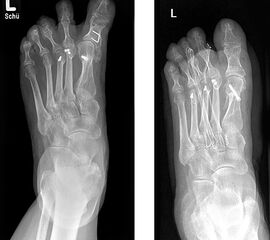

Radiologische Diagnostik

11"> Der Hallux varus Winkel  <a class=11" title="Der Hallux varus Winkel 11" srcset="/assets/images/2/4-vk3bypbg5s5x7zc.jpg 1x, /assets/images/3/4-aax2sd1hrpnrvrb.jpg 1.452x" width="270" height="240" loading="lazy">

Abbildung 3

Die bildgebende Diagnostik hilft bei der Klärung der Ätiologie und des Ausmaßes der Fehlstellung. Hierzu sind Röntgen­aufnahmen im Stand in mindestens zwei Ebenen unter Belastung des Fußes erforderlich. Mit Hilfe der belasteten Röntgenaufnahmen wird der Hallux-varus-Winkel, d. h. den Winkel zwischen der Achse der Grundphalanx der Großzehe und der Achse des ersten Mittelfußknochens bestimmt, sowie etwaige Rotationsfehlstellungen des 1. Strahls verifiziert. Eventuelle knöcherne Fehlanlagen bei kongenitalen Deformitäten können hierdurch ebenfalls verifiziert werden.

Weitere Beurteilungskriterien sind:

• degenerative Veränderungen des MTP I

• Kongruenz des MTP I- Gelenkes

• Form und Stellung des Mittelfußköpfchens I

• Ausprägung der Pseudoexostose.

• PASA-Winkel, d. h. der periphere Artikulationswinkel des Großzehengrundgelenkes.

Zur Klärung der Ätiologie wird der intermetatarsale Winkel zwischen Os metatarsale I und II bestimmt. Ist dieser kleiner als 5° oder gar negativ, ist eine Varusstellung der Großzehe oft die Folge.

Am Röntgenbild des belasteten Fußes bestimmt man die Lage der Sesambeine zum 1. Mittelfußköpfchen.

Anhand der Röntgenaufnahme lassen sich die Folgen einer eventuellen Voroperation bestimmen, wie z. B. die Stellung des ersten Mittelfußköpfchens, des ersten Metatarsale nach Korrekturen der Achse bei einer Hallux-valgus-Operation. Mitunter bestehen Nekrosen des Mittelfußköpfchens oder eine übermässige Resektionen der Pseudoexostose. Auch die Länge des 1. Metatarsale kann von Interesse sein, z. B. nach einer Lapidusarthrodese (Johnson 1994).